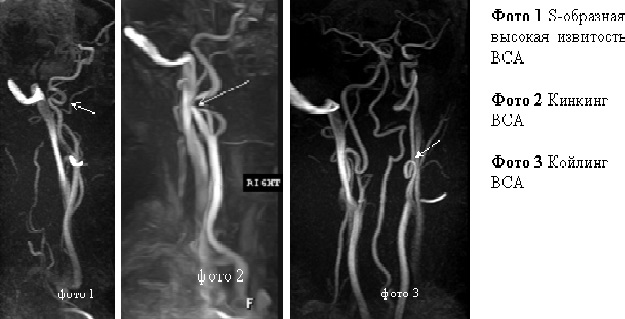

С изгиб вса

С изгиб вса 113 фото